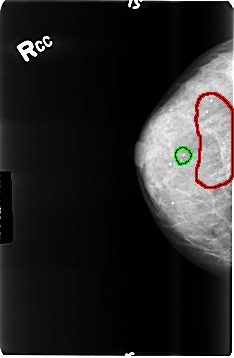

B_3496_1.RIGHT_CC

FILE: B_3496_1.RIGHT_CC.OVERLAY

TOTAL_ABNORMALITIES 2

ABNORMALITY 1

LESION_TYPE CALCIFICATION TYPE PUNCTATE-AMORPHOUS DISTRIBUTION REGIONAL

ASSESSMENT 4

SUBTLETY 4

PATHOLOGY BENIGN

TOTAL_OUTLINES 1

BOUNDARY

ABNORMALITY 2

LESION_TYPE CALCIFICATION TYPE PUNCTATE-AMORPHOUS DISTRIBUTION CLUSTERED